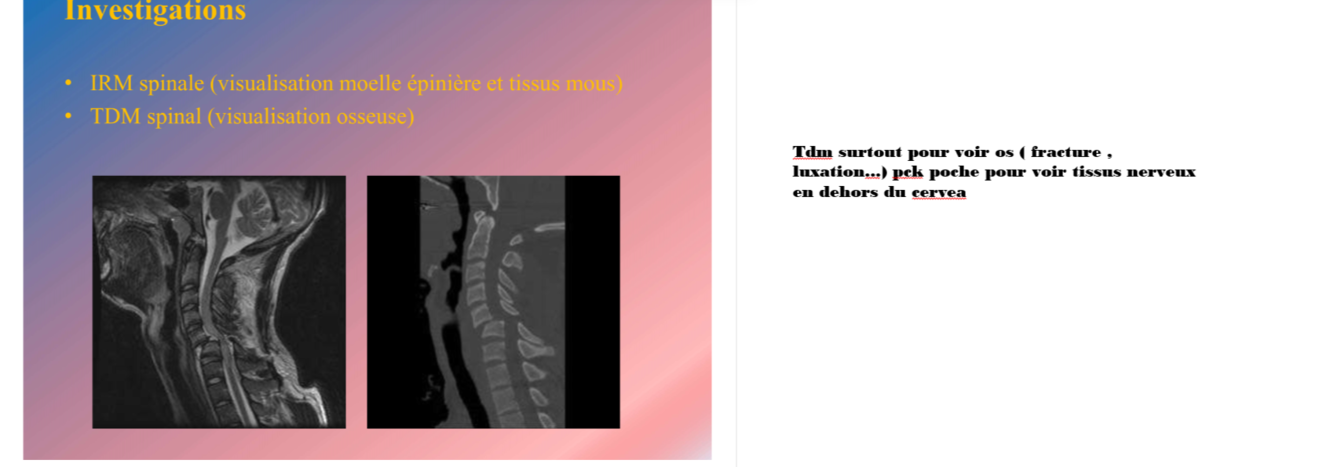

quel test d’imagerie pour traumatisme médullaire?

A

TDM ( plus pour os, poche pour tissu nerveux en dehors du cerveau) et IRM ++